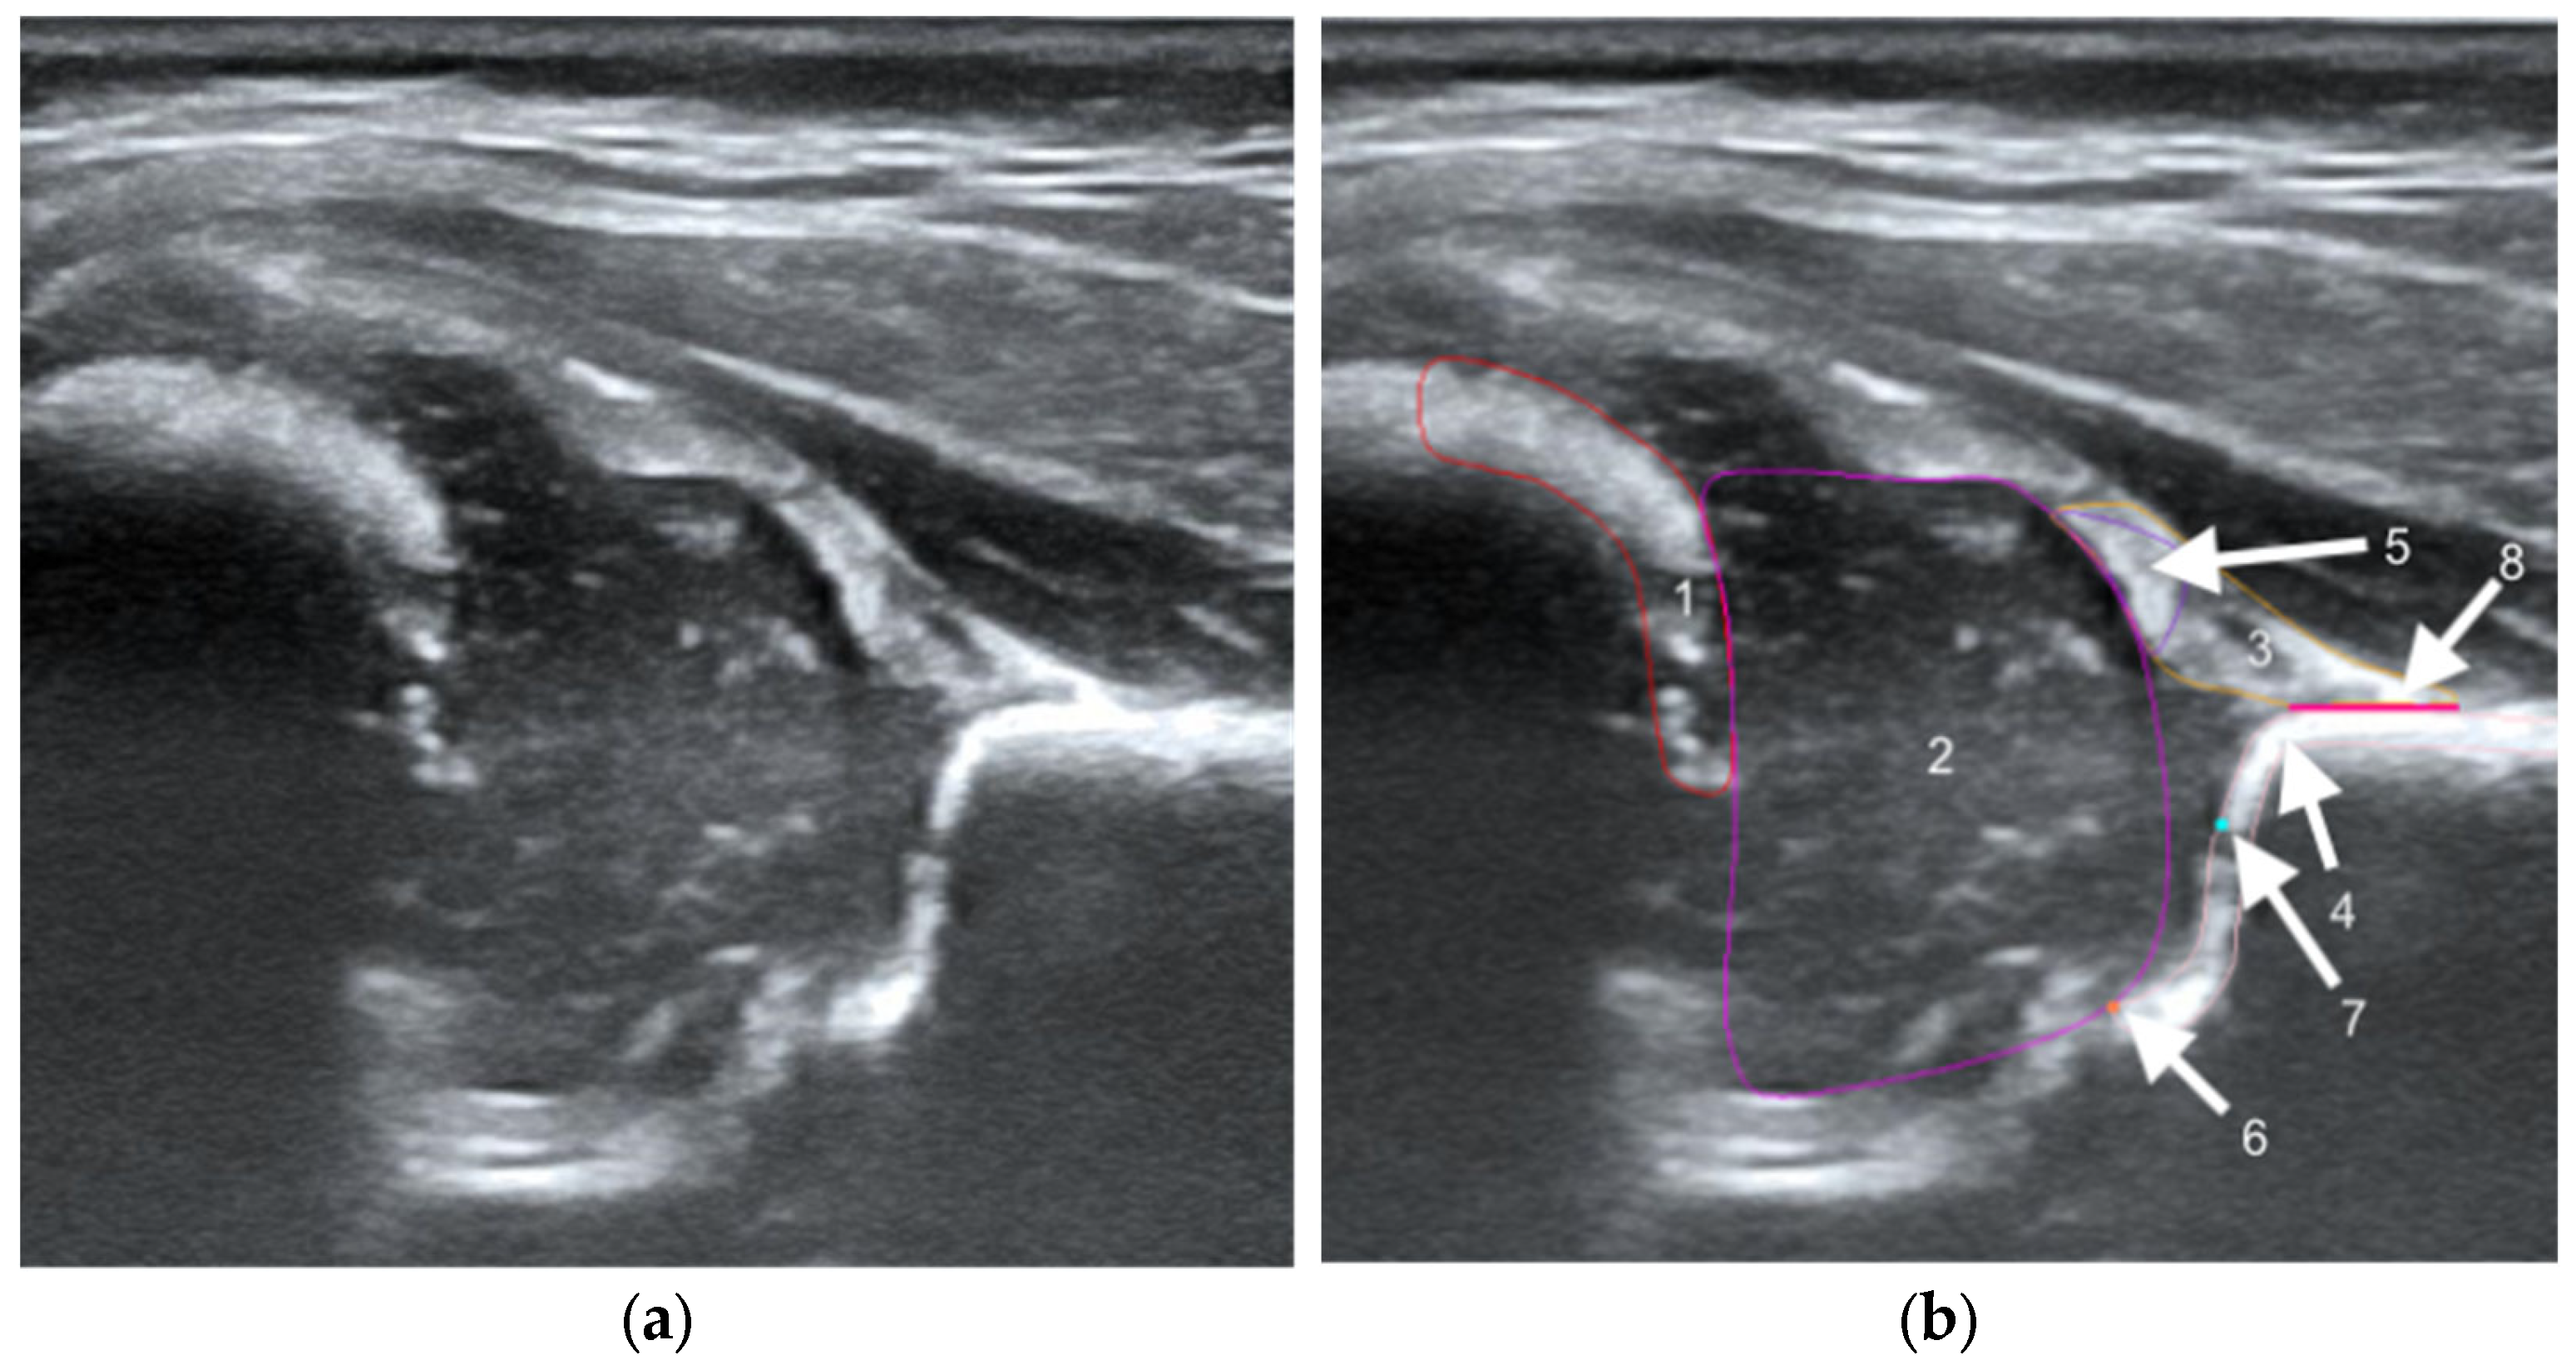

To illustrate the performance of the segmentation model, a comparison is presented between the labels obtained by the segmentation model and the ground truth labels. Two models were analyzed: Model-8 (generating segments for eight classes) and Model-5 (generating segments for five classes). Both the cases with the highest quality model labels and the cases where the model labels were less accurate are presented. Figure 3 shows one of the best cases, in which Model-5 and Model-8 accurately labeled the classes relative to the doctor’s labels. The worst-case scenario was also analyzed, in which the prediction results differ significantly from the ground truth labels (Figure 4).

Figure 4. Low-quality model labels (upper—Model-8) and (lower—Model-5). Annotated mask on the left, model mask on the right.